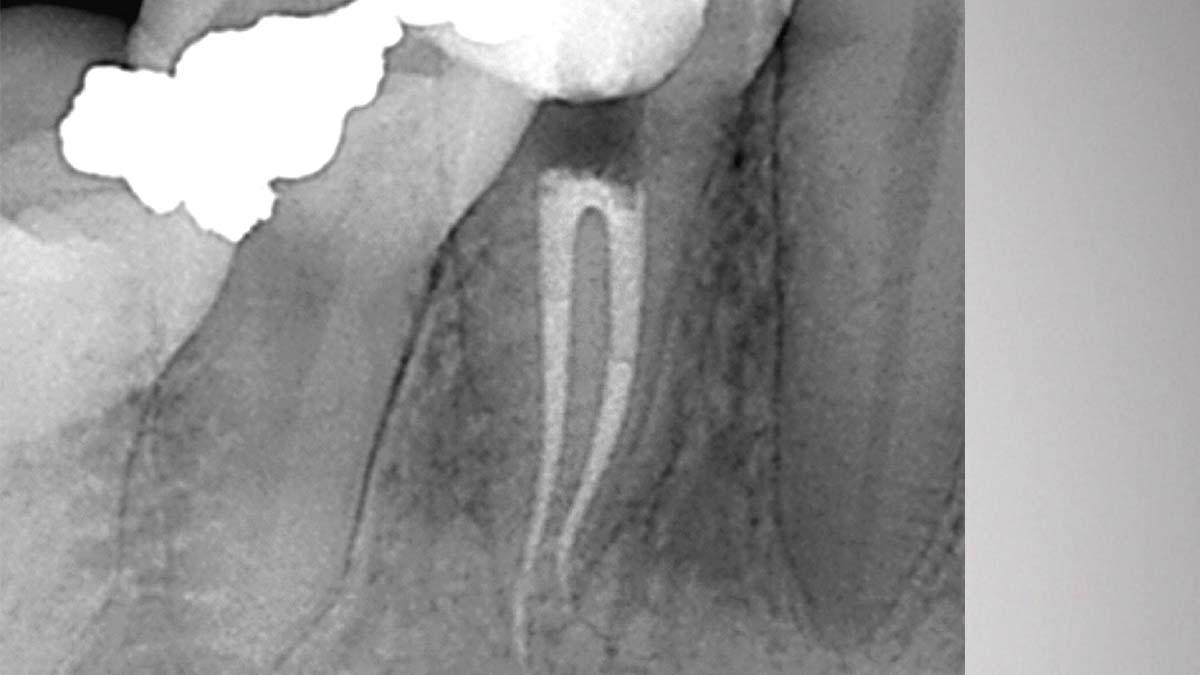

On the right: Gutta-Smart and Conform Fit feature the same advanced gutta-percha for radiographic consistency.

Image courtesy of Dr. Nathaniel Behrents, Fayetteville, AR